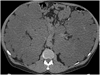

Patients with polycystic kidney disease (PKD) are at elevated risk of new-onset atrial fibrillation (AF), according to researchers.

In a population-based cohort study using inpatient claims data from Taiwan's National Health Insurance Research Database (NHIRD), investigators found that PKD patients had a  significant 31% increased risk of AF compared with individuals who did not have PKD, after adjusting for age, sex, and comorbidities. The risk was higher in patients aged 50 to 64 years and those without any comorbidities, “suggesting that the development of AF in patients with PKD is highly associated with the disease itself,” the investigators reported in Medicine (2016;95:e2623).